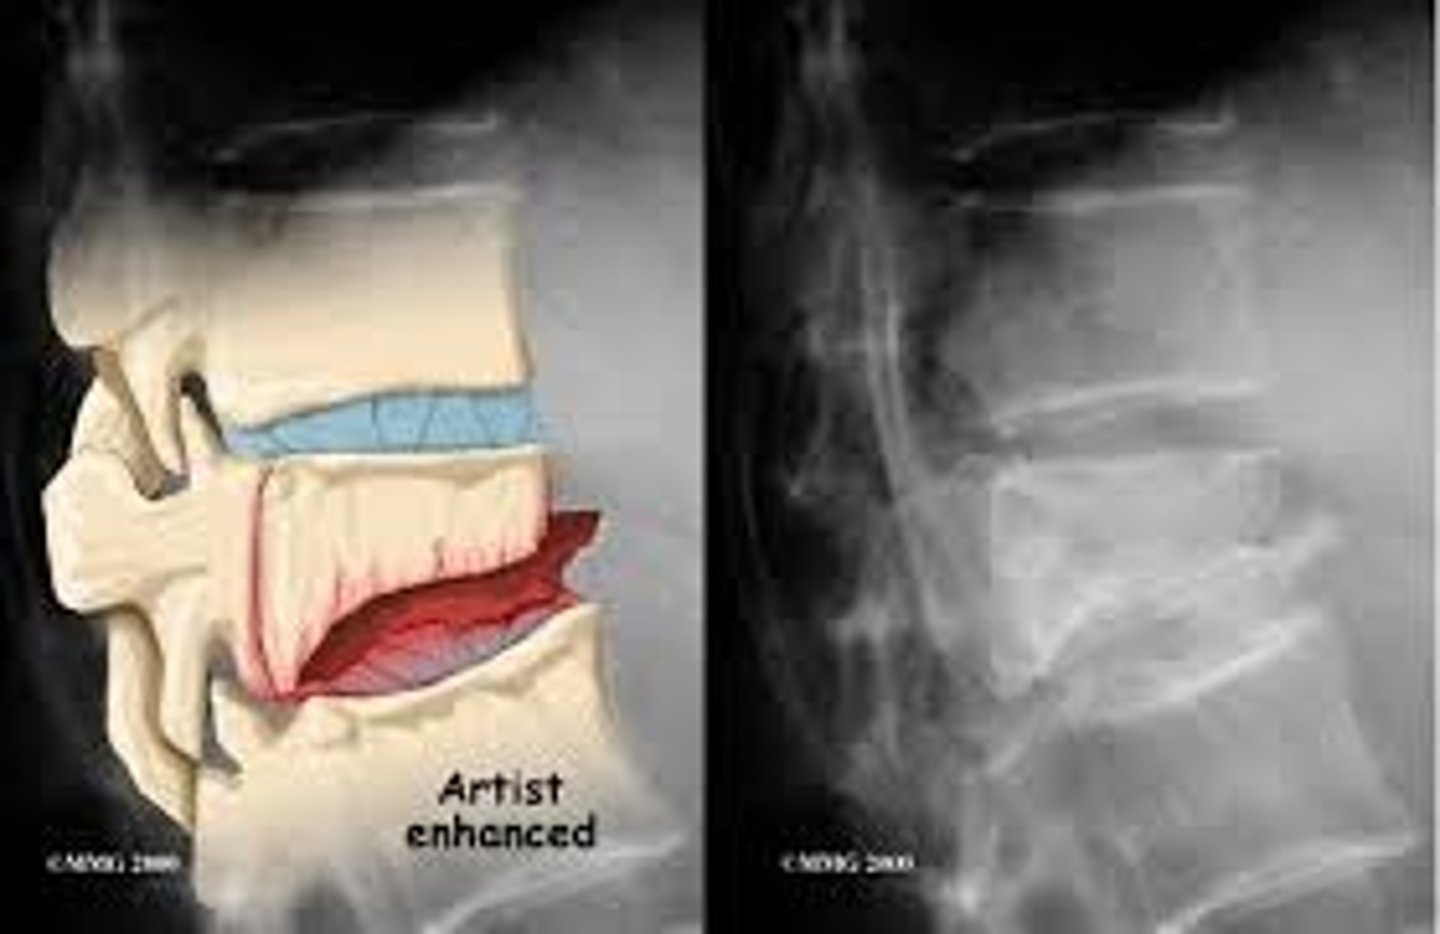

herniated disks

degeneration of outer annular fibers, caused by acute compression of nerve root

MRI is study of choice

compression fractures

collapse of vertebrae, usually secondary to osteoporosis, no neuro deficit, wedge-shaped deformity